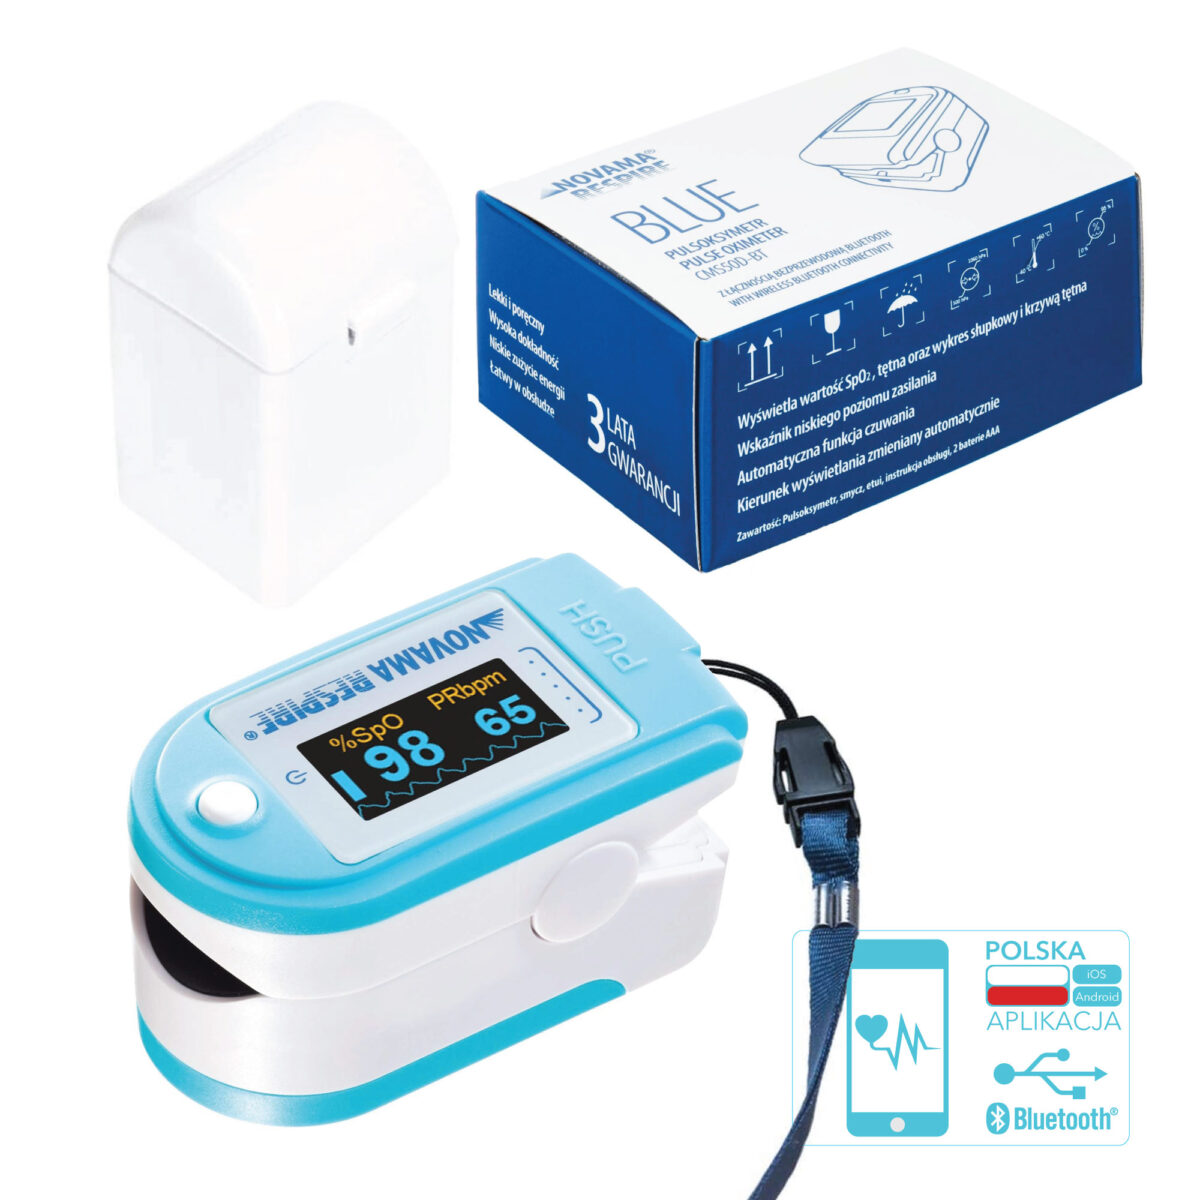

Pulsoksymetry napalcowe

Pulsoksymetry napalcowe to najpopularniejszy i najczęściej stosowany typ tych urządzeń. Są kompaktowe, lekkie i przenośne, dzięki czemu doskonale sprawdzają się zarówno w warunkach domowych, do samodzielnego monitorowania saturacji, jak i w placówkach medycznych, gdzie służą personelowi do szybkiej oceny stanu zdrowia pacjenta.

Urządzenie swoim kształtem przypomina klips, który zakłada się na palec, najczęściej wskazujący, środkowy lub serdeczny. Po umieszczeniu palca pomiędzy gumowe poduszeczki wynik pomiaru saturacji oraz tętna pojawia się na wyświetlaczu już po kilku sekundach.

Pulsoksymetry napalcowe są proste w obsłudze i zazwyczaj zasilane bateriami, co pozwala na ich wygodne bezprzewodowe użytkowanie w dowolnych warunkach – w domu, w podróży czy podczas pracy personelu medycznego.

Czytelny i ergonomiczny wyświetlacz jest kluczowym elementem pulsoksymetru, wpływającym na wygodę i szybkość odczytu wyników. Duży, podświetlany ekran z wysokim kontrastem pozwala na łatwe odczytanie danych w różnych warunkach oświetleniowych. Wiele nowoczesnych modeli oferuje dwukolorowy wyświetlacz, możliwość zmiany kierunku wyświetlania (obrót o 90° i 180°) oraz regulację jasności, co dodatkowo poprawia komfort użytkowania. Nowoczesne pulsoksymetry często wykorzystują technologię OLED (Organic Light Emitting Diode), która zapewnia wyraźny obraz przy niskim zużyciu energii, umożliwiając dłuższą pracę bez konieczności częstej wymiany baterii.

Dodatkowe funkcje

Nowoczesne pulsoksymetry oferują szereg dodatkowych funkcji, które zwiększają wygodę i bezpieczeństwo użytkowania. Do najpopularniejszych należą możliwość zapamiętywania wyników pomiarów oraz synchronizacja z aplikacją na telefon, co pozwala na monitorowanie i analizę trendów saturacji (SpO₂) i tętna w dłuższym okresie. Dane te mogą być następnie udostępniane personelowi medycznemu lub członkom rodziny, co wspiera zdalną opiekę nad pacjentem.

Wiele urządzeń wyposażonych jest w algorytmy tolerancji ruchu lub funkcję „antimotion”, które minimalizują ryzyko błędów pomiarowych spowodowanych lekkim drżeniem dłoni. Zaawansowane technologie detekcji umożliwiają dokładny pomiar nawet przy niskiej perfuzji.

W trosce o bezpieczeństwo użytkowników coraz częściej stosuje się sygnalizację dźwiękową lub wizualną, ostrzegającą o spadku saturacji poniżej określonego poziomu lub o nieprawidłowej częstości tętna. Dodatkowe udogodnienia obejmują także wskaźnik poziomu baterii, tryb oszczędzania energii oraz automatyczne wyłączanie urządzenia po zakończeniu pomiaru lub kilku sekundach bezczynności, co wydłuża czas pracy na jednym źródle zasilania